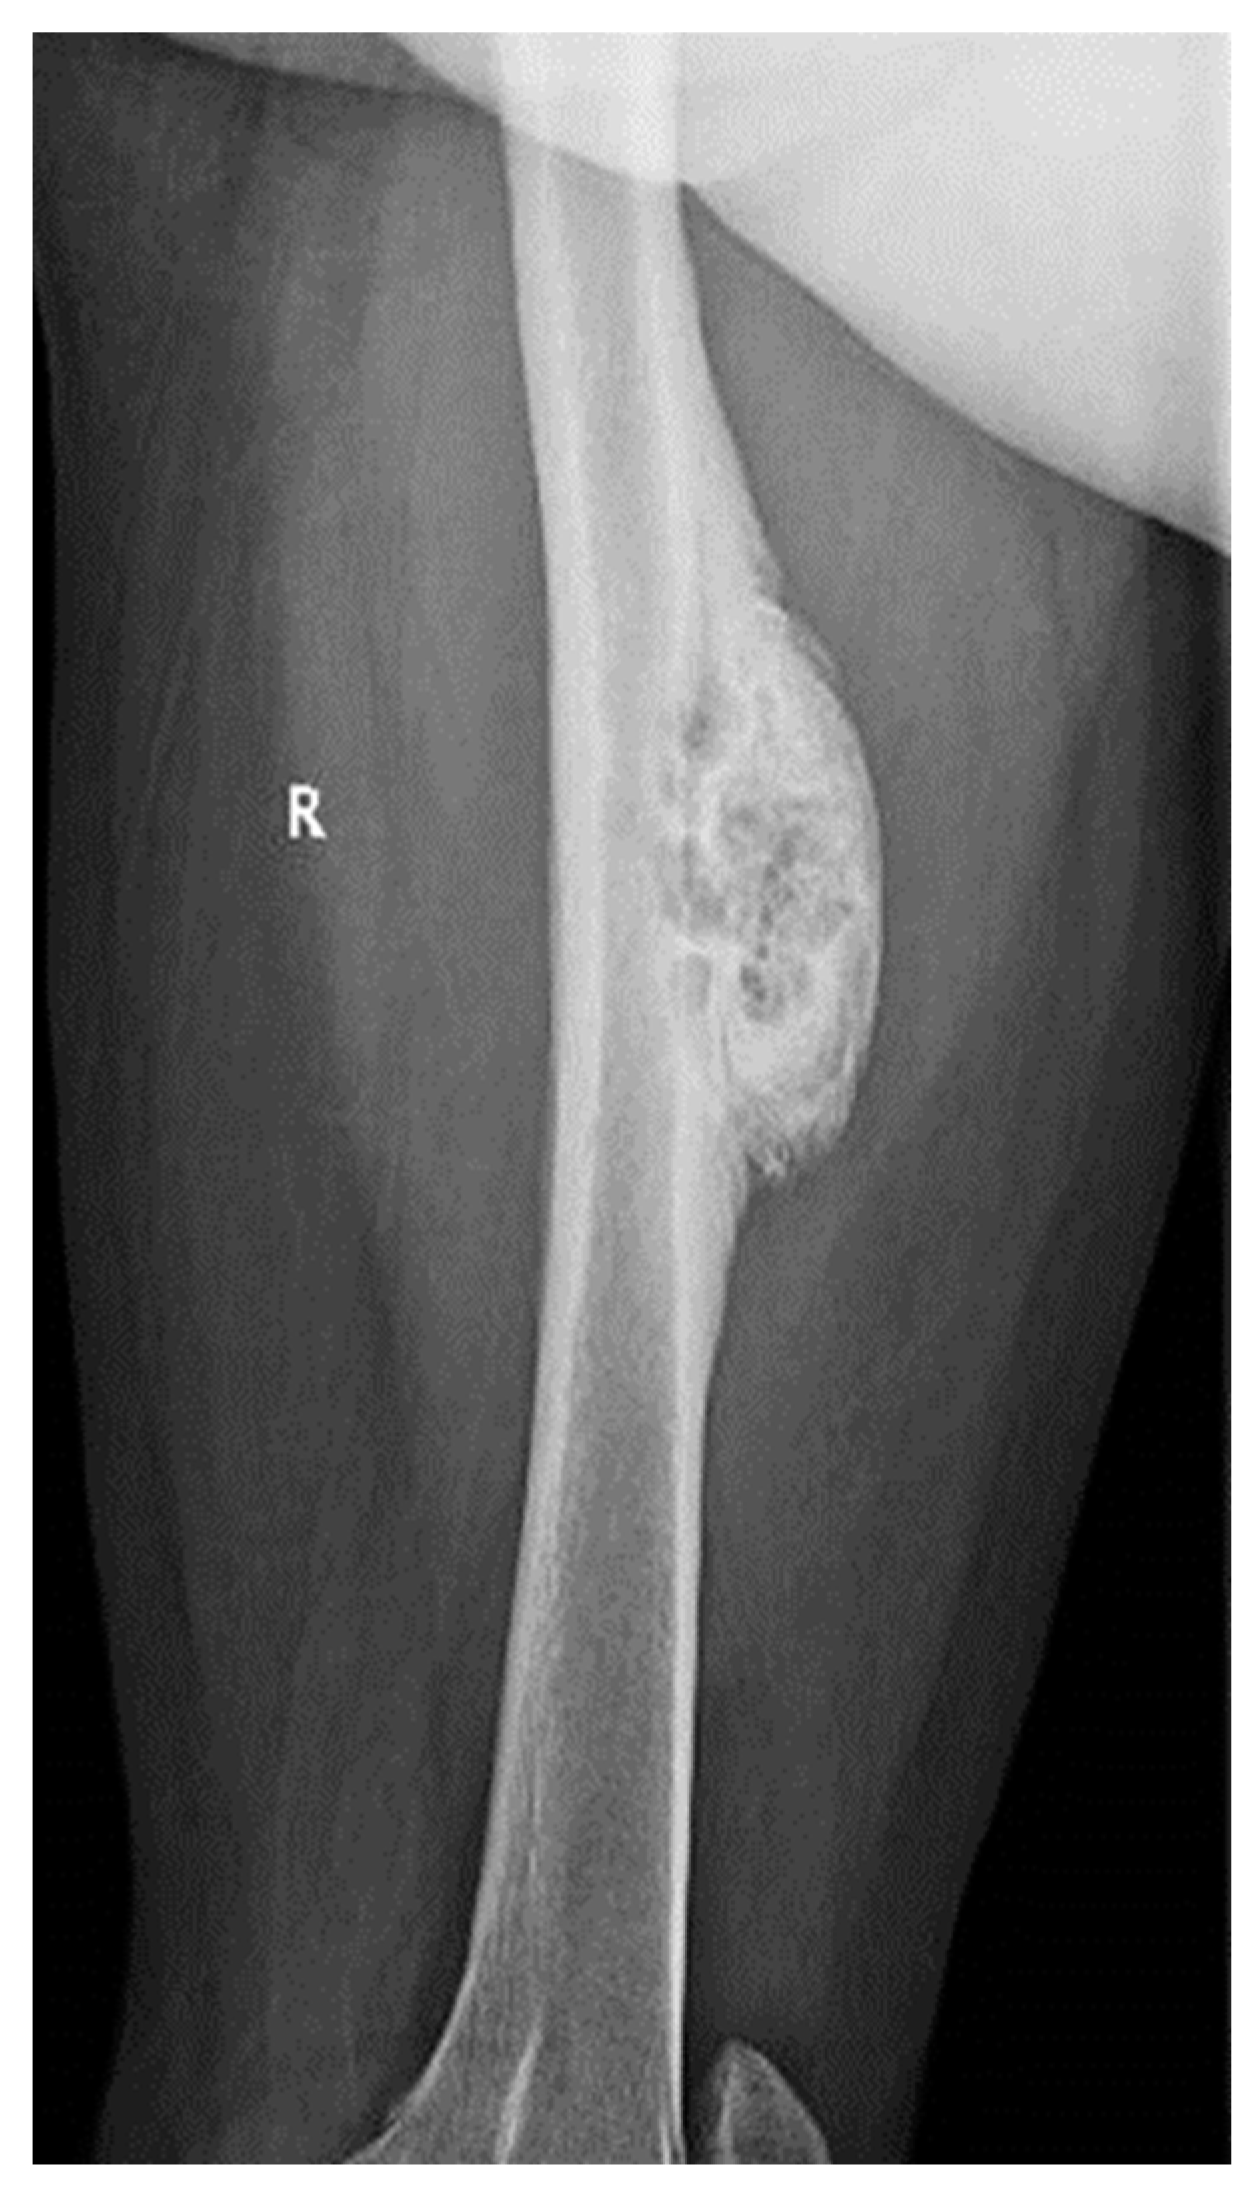

We present the case of a 46-year-old female patient who presented to the orthopedics and traumatology department of the University Emergency Hospital of Bucharest with severe pain in the left thigh and limitation of joint mobility. Following the clinical examination, the patient complained of pain in the middle third of the left thigh in the antero-medial part; the pain appeared spontaneously and was aggravated during physical activity. The pain started about two years ago, but the patient experienced complete pain relief after the administration of non-steroidal anti-inflammatory drugs. In the last six months, the patient presented an increase in pain intensity without significant improvement following the administration of non-steroidal anti-inflammatory drugs. The patient used non-steroidal anti-inflammatory drugs daily, without a significant improvement in pain, which significantly affected her quality of life. No shortening of the limbs or stiffness in the adjacent joints was observed. At the local examination, the patient had normal skin, without local changes, without inflammatory signs present, and no signs of ischemia. An X-ray of the femur in the antero-posterior and lateral incidence was performed which identified a unique bone lesion with dimensions of approximately 12/10 cm in the coronal plane located on the antero-medial cortex of the femur with a mixed appearance (Figure 1 and Figure 2). After that, we performed a whole-body scintigraphy which highlighted the same bone lesion described in the radiological examination with moderate uptake in the late phase, without highlighting other associated bone lesions.

Figure 1. Full-leg X-ray in the antero-posterior view showing a sclerotic bone lesion (12 cm) associated with lytic areas with thickening of the bone cortex.

Figure 2. Lateral view X-ray of the femur showing sclerotic bone associated with lytic areas with thickening of the bone cortex.